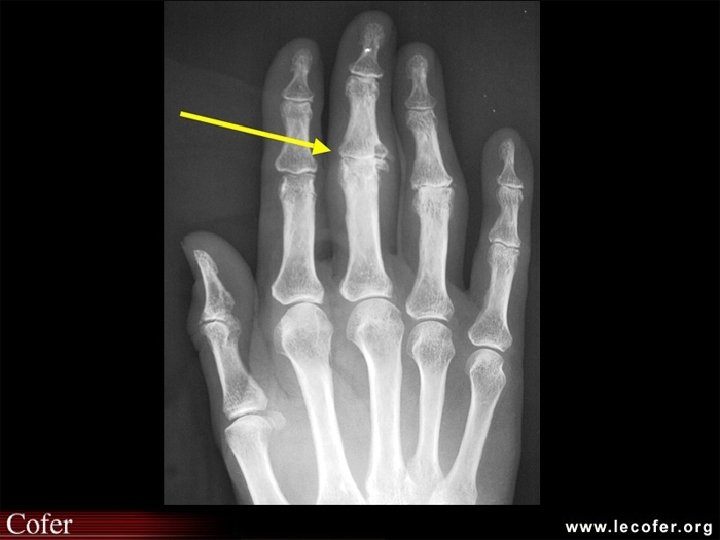

Comment faire le diagnostic ? • Le diagnostic est clinique : déformations typiques • Les radiographies : mains de face – pincement de l’interligne – une ostéophytose latérale en berge, très exubérante responsable des nodosités – géodes sous-chondrales